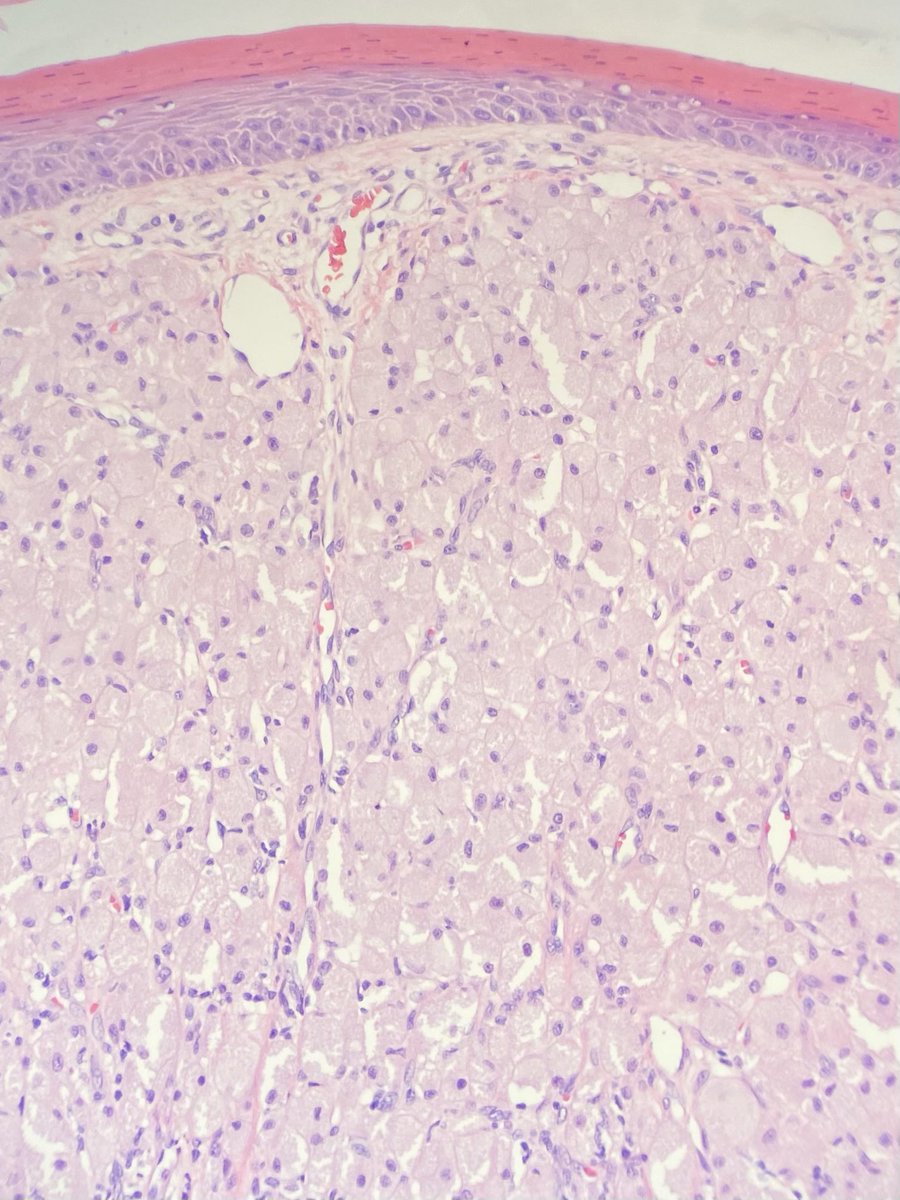

Diabetic Drama: 26 yo M with no PMH a/w 2 weeks severe nausea, vomiting, dehydration. Glucose was 1200!! (new onset DM/DKA?) and potassium 1.5. Anuric renal failure requiring HD. Bx shows ATN and rhabdomyolysis! No significant diabetic changes.  Is this rhabdo 2/2 DKA? COVID neg.